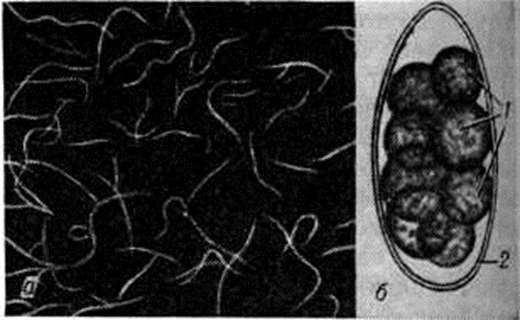

ТрихостронгилоидозТрихостронгилоидоз (trichostrongyloidosis; синонимы трихостронгилидоз) — гельминтоз из группы нематодозов, характеризующийся преимущественно нарушением функции желудочно-кишечного тракта. Трихостронгилоидоз встречается в ряде стран Азии, Африки, Америки, Европы. Первый случай Трихостронгилоидоз в СССР был описан в 1924 год В. П. Подъяпольской. Почти на всей территории нашей страны регистрируются единичные случаи Трихостронгилоидоз В некоторых горных скотоводческих районах Армении и Азербайджана Трихостронгилоидоз встречается чаще. Возбудителем Трихостронгилоидоз являются мелкие нематоды из семейство трихостронгилид (Trichostrongylidae Leiper, 1912), среди которых выделяют 12 видов. У человека Трихостронгилоидоз в большинстве случаев обусловлен инвазией двух видов — Трихостронгилоидоз orientalis и Трихостронгилоидоз colubriformis. Все остальные виды трихостронгилид обычно инвазируют жвачных животных и у человека паразитируют редко. Трихостронгилиды — нитевидные нематоды длиной около 5 миллиметров(рисунок, а). Виды трихостронгилид различаются по особенностям строения тела самцов. Трихостронгилиды — геогельминты (смотри полный свод знаний). Их облигатными хозяевами являются многие травоядные животные, главным образом крупный и мелкий рогатый скот, в пищеварительном тракте которых они паразитируют. У человека (факультативного хозяина) трихостронгилиды паразитируют в тонкой кишке, чаще в двенадцатиперстной кишке, проникая своим передним концом в слизистую оболочку. Самки трихостронгилид откладывают сегментированные яйца длиной 0,075—0,118 миллиметров, содержащие 8—24 бластомера (рисунок, б); яйца попадают в окружающую среду с фекалиями. При благоприятных условиях в яйцах в течение нескольких суток развиваются рабдитовидные личинки. В дальнейшем личинка дважды линяет и превращается в инвазионную филяриевидную личинку с чехликом. Проглоченная животным или человеком инвазионная личинка в кишечнике претерпевает ещё две линьки и, не совершая миграции, развивается в зрелого паразита приблизительно через 3 недель после заражения. Указывают на возможность длительного, до 8 лет и более, течения этой инвазии. Интенсивность инвазии может быть высокой — до 4 тысяч трихостронгилид. Источником возбудителей инвазии являются травоядные животные (овцы, козы, крупный рогатый скот), поражённые Трихостронгилоидоз и загрязняющие фекалиями, в которых содержатся яйца гельминтов, пастбища, стойла и другие Яйца развиваются в почве при t° от 4 до 38°. Филяриевидные личинки могут длительное время сохраняться в почве, на овощах; они способны к миграции по стеблям растений (до 60 сантиметров вверх). Человек заражается, проглатывая личинки с водой, пищей или занося их в рот загрязнёнными руками. Люди, имеющие привычку брать в рот сорванные на пастбищах растения, подвергаются опасности заражения трихостронгилоидозом. Патогенез болезни изучен мало. Трихостронгилиды, внедряясь в слизистую оболочку тонкой кишки, вызывают расстройства пищеварения, аллергические реакции, способствуют развитию дискинезии кишечника, энтерита и холецистопатии. Обычно выраженные явления энтерита (смотри полный свод знаний: Энтерит, Энтероколит) развиваются при большом количестве паразитов. Больные часто жалуются на расстройство аппетита, тошноту, запоры или понос, боли в животе, общую слабость и раздражительность. Отмечается бледность кожи и слизистых оболочек, иногда исхудание, болезненность при пальпации живота, в крови резко выраженная эозинофилия, иногда гипохромная анемия. Окончательный диагноз Трихостронгилоидоз основывается на выявлении яиц паразита (иногда самих гельминтов) в фекалиях больных или в дуоденальном содержимом. Яйца трихостронгилид несколько похожи на яйца анкилостомид (смотри полный свод знаний: Анкилостомидозы), однако последние меньших размеров и содержат не более 8 бластомеров. Лечение проводят нафтамоном, мебендазолом (вермоксом), комбантрином и левамизолом (декарисом). Наибольшей терапевтической эффективностью (до 100%) обладает вермокс, назначаемый внутрь в течение 3 дней в суточной дозе 200 миллиграмм (в два приёма). По мере необходимости назначают общеукрепляющие и антианемические средства. Прогноз благоприятный. |

Рис | ||